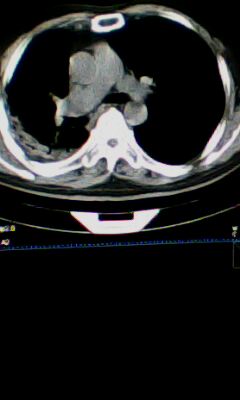

标题: CT25675:男 71 肺癌部分切除术后 3年 [打印本页]

标题: CT25675:男 71 肺癌部分切除术后 3年

1)两肺感染性病变。2)右侧胸膜增厚。3)冠状动脉及主动脉钙化。

1.右肺符合肿瘤切除术后ct表现。

2.左肺炎症。

术后改变,双肺内纤维索条影考虑与放疗有关。